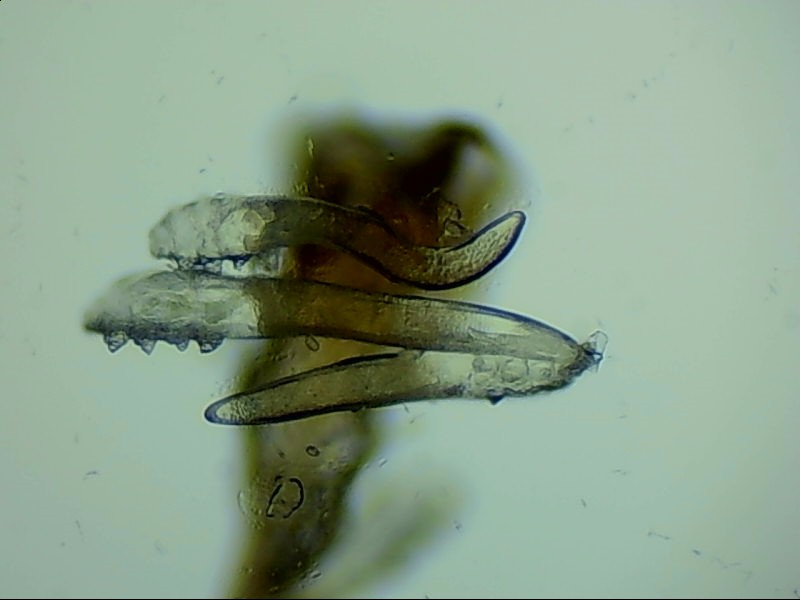

蠕形螨是螨蟲的一種,主要寄居在毛囊中。蠕形螨以分泌的油脂、分泌物為食,所以眼部寄居著蠕形螨的患者多有亂睫或睫毛脫落的癥狀。

蠕形螨寄居后,它們以睫毛毛囊里面的油脂為食。隨著油脂的缺失,睫毛會(huì)長(zhǎng)的東倒西歪,如果毛囊里的油脂都被吃光了,就會(huì)出現(xiàn)睫毛脫落這種蠕形螨性瞼緣炎的典型癥狀。